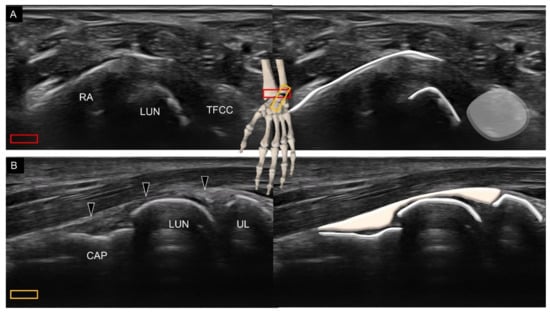

2. Sonoanatomy of Carpal Bones

3.2. Attachment to the Lunate